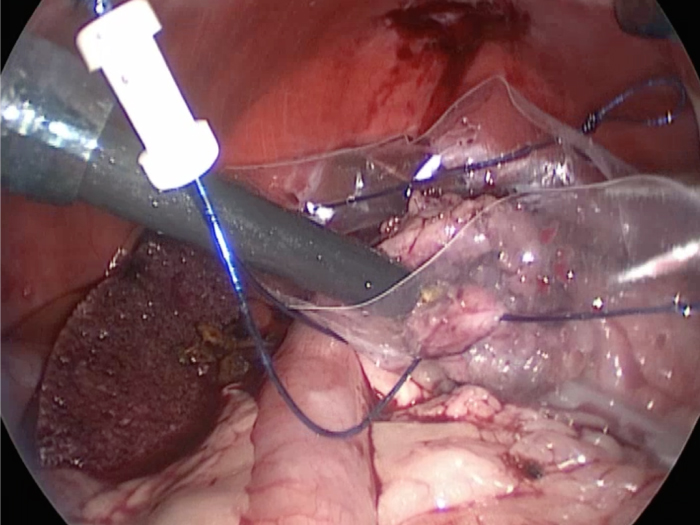

他院より紹介。胆嚢炎がひどく繰り返す嘔吐がありました。 腹膜と一部横隔膜に胆嚢ががっちりと癒着していました。 体重が2kgと体も小さかったのですが、飼い主さんの希望もあり、腹腔鏡下で手術を実施することになりました。

丁寧に丁寧に出血をコントロールしながら少しずつ手術をすすめていきます。

癒着(矢印)がひどく胆嚢を確認することができませんでした。

このように癒着しているときはギリギリで剥がすとひどく出血をおこすことがあるので無理にはがそうとしないで、脂肪の血管に注意しながら脂肪ごと剥がしていきます。

胆嚢の通路がちゃんと開通しているのか調べるために造影検査をしています。

この処置をすることで洗浄の効果と詰まりを確認することができます。